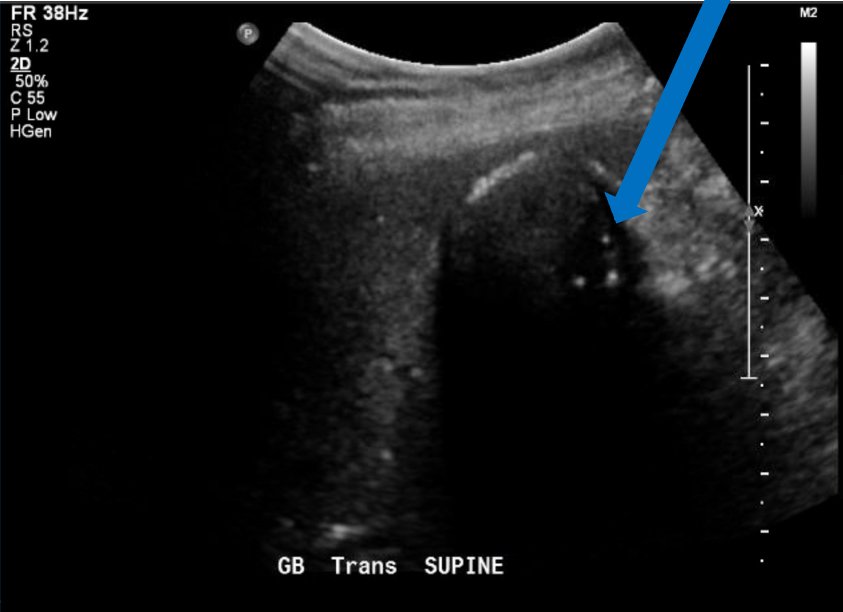

A 75-year-old female presented for evaluation of elevated liver function tests (LFTs). Upon arrival, she had no acute complaints with unremarkable vital signs, aside from elevated blood pressure of 155/79 mmHg. Review of LFTs demonstrated elevation of total bilirubin, aspartate aminotransferase (AST), alanine aminotransferase (ALT), and alkaline phosphatase (ALP). Physical examination and review of systems were unremarkable. POCUS revealed common bile duct dilatation with cholelithiasis and sludge. While these findings may be confused with a WES sign, POCUS also revealed a hyperechoic gallbladder wall (GBW) with shadowing and irregular clumps of echo. The hyperechoic GBW with irregular shadowing heightened the suspicion for PGB. Computed tomography scan confirmed the presence of PGB. The patient had a stent placed near the common hepatic duct stricture and was advised to return for cholecystectomy. She was readmitted three months later due to bacteremia, likely caused by gallbladder obstruction in the setting of gallbladder cancer.

Point of care ultrasound can be used to identify PGB. Because PGB has been associated with gallbladder carcinoma, prompt diagnosis is vital in early and aggressive treatment. In this case report, we demonstrate a reliable method in properly diagnosing PGB through POCUS.